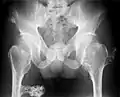

Multiple osteochondromas at the pelvis -